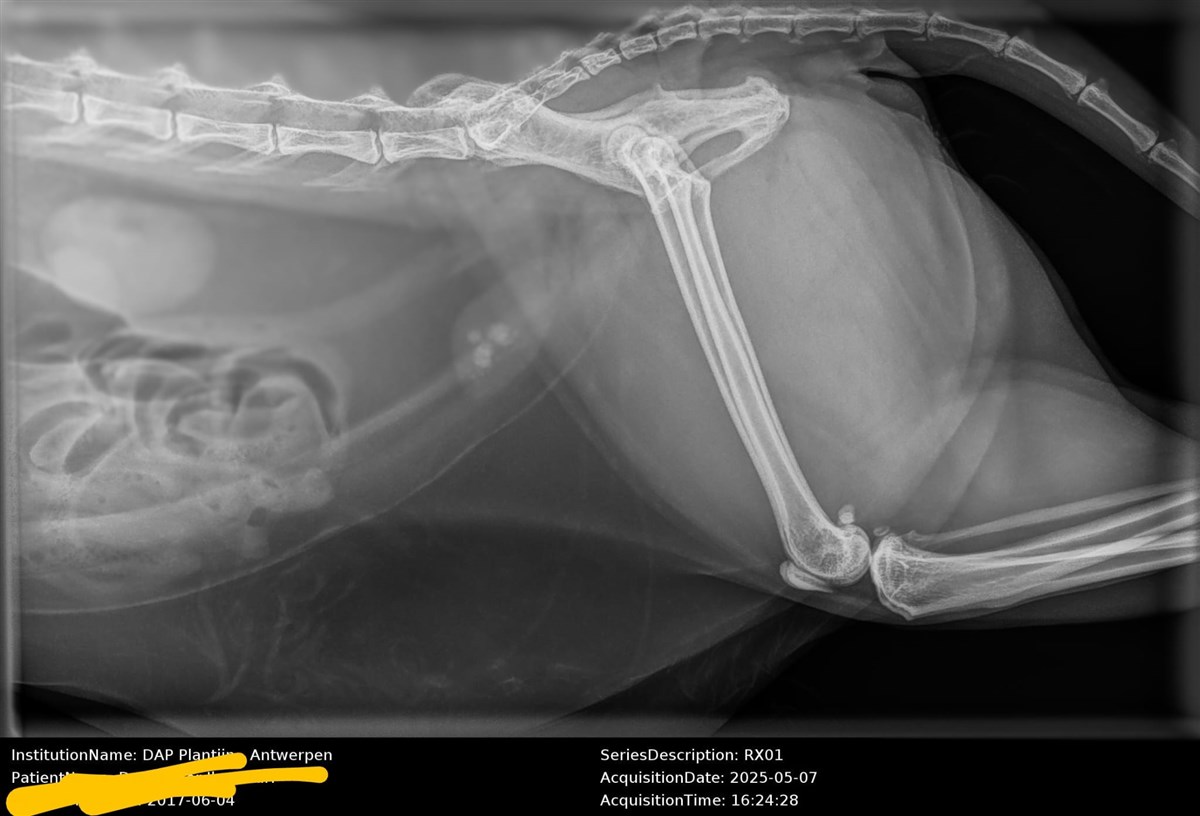

Bij de dierenarts werd vastgesteld dat Xari blaasstenen heeft. Zonder operatie komt haar leven in gevaar. De ingreep kost €600 - een bedrag dat het gezin momenteel onmogelijk zelf kan opbrengen.